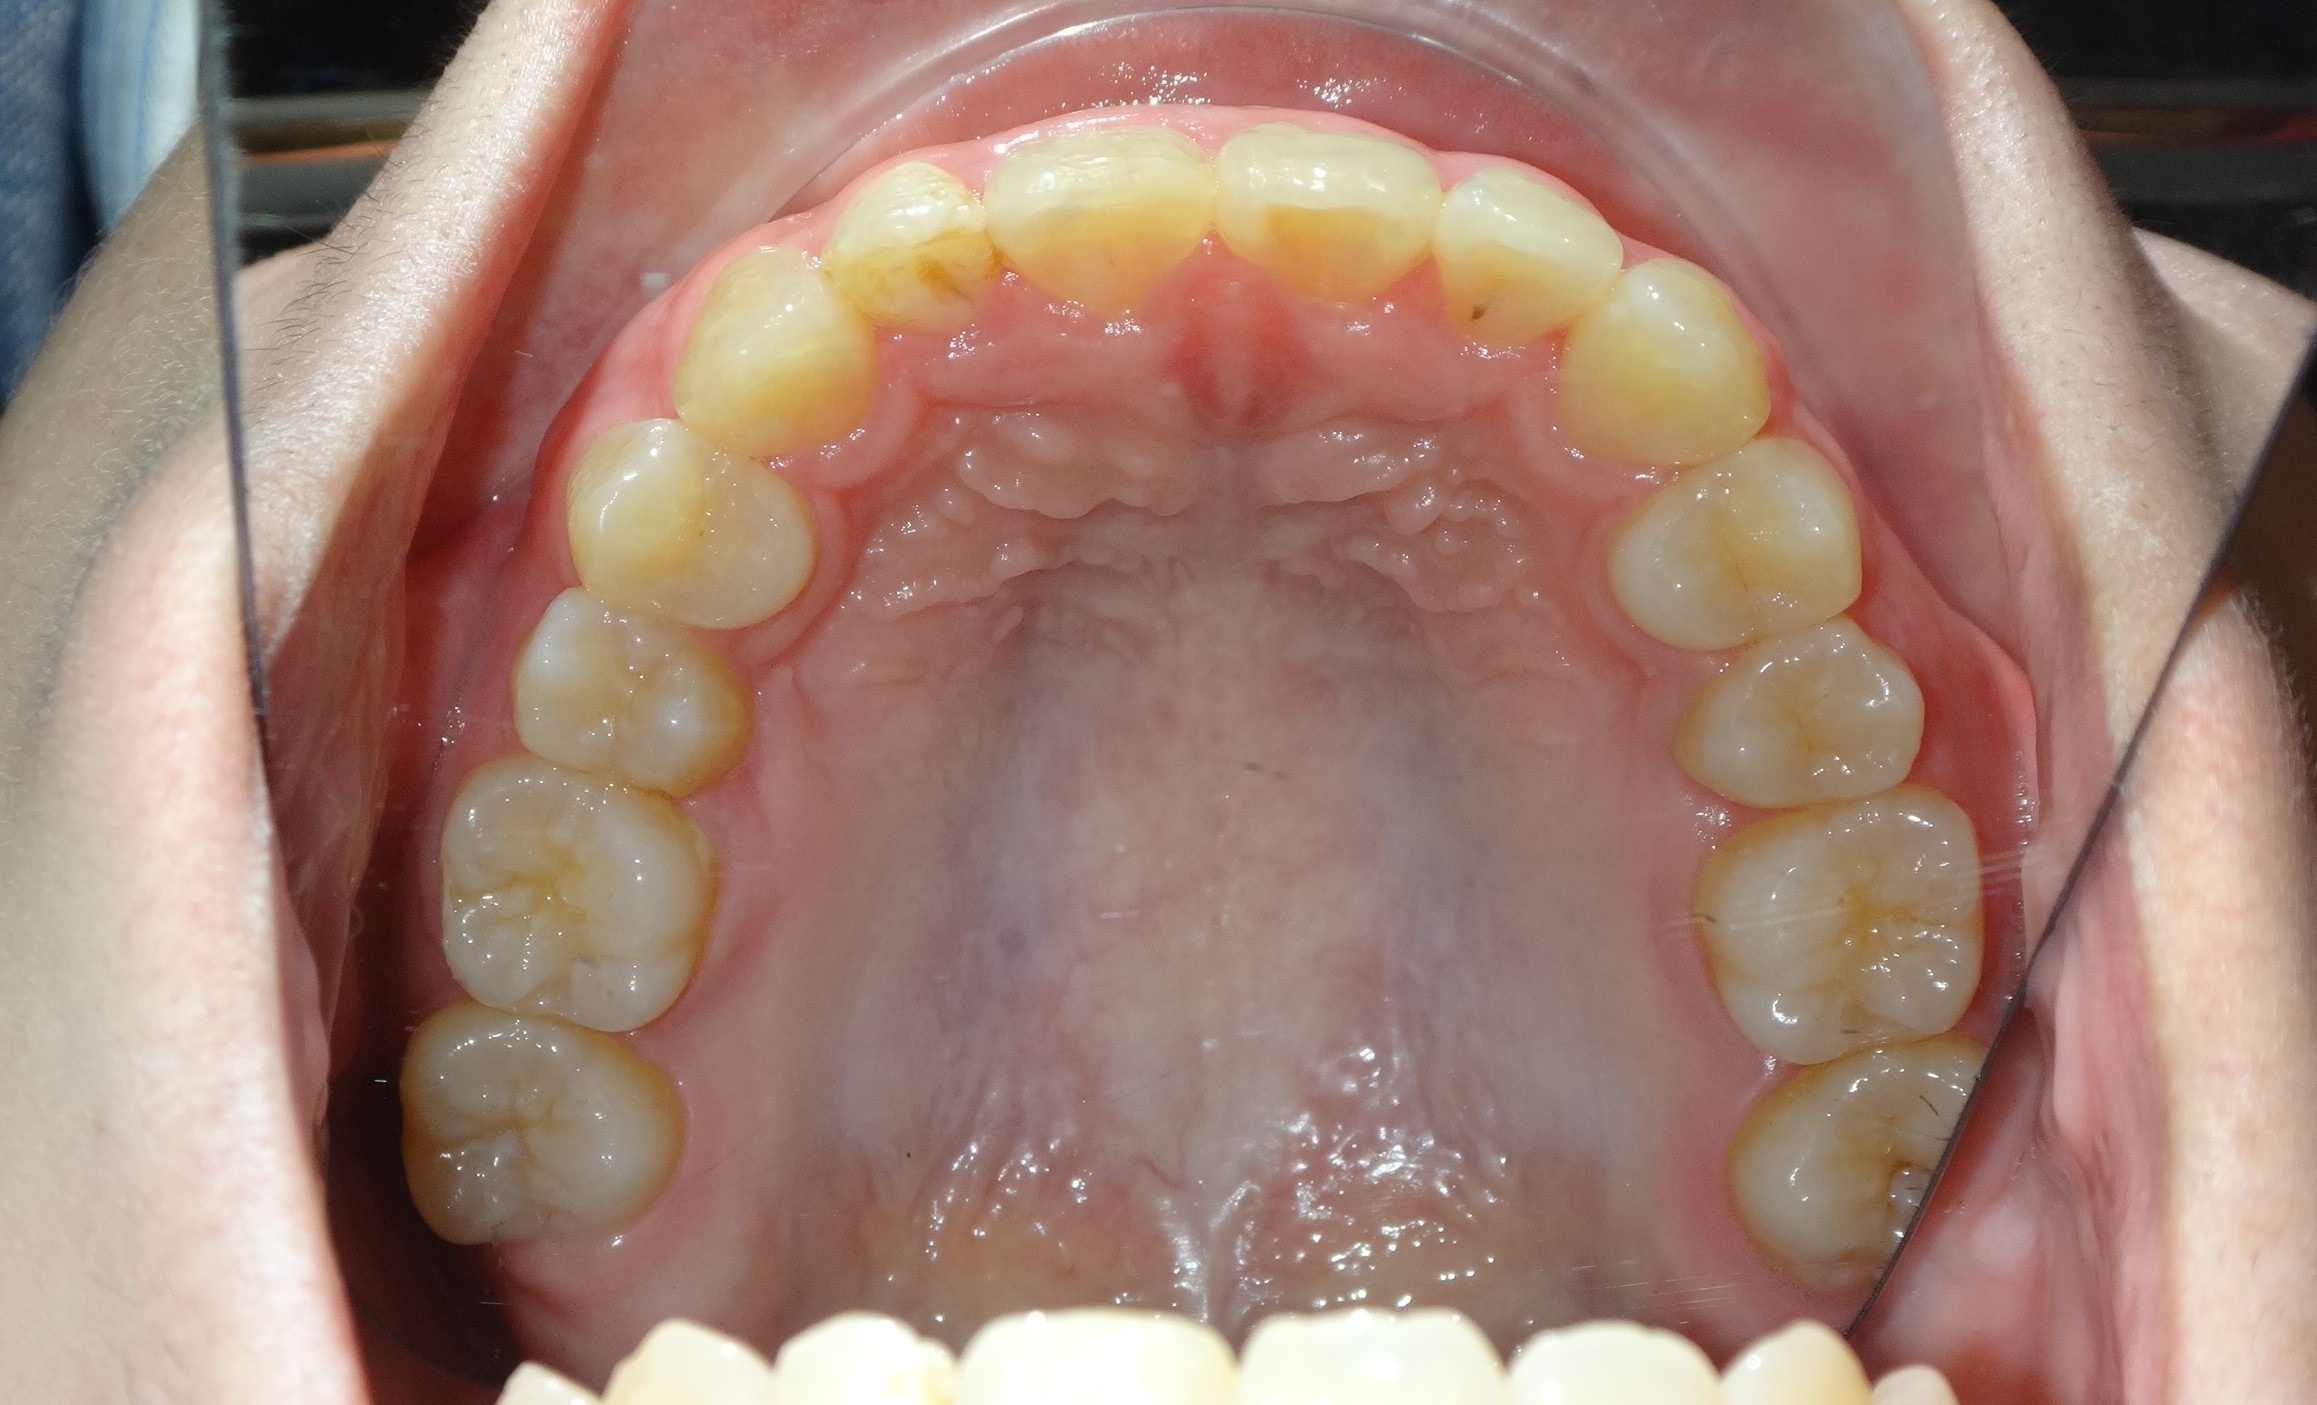

不拔牙案例 首頁 案例分享 齒顎矯正 不拔牙案例 - 矯正不拔牙案例 - 年紀:27歲 治療方式:隱適美隱形矯正 時間:34個月 主訴:前牙錯咬、排列不整 矯正前 矯正後 矯正前 矯正後 矯正前 矯正後 聲明:本所療程皆由專業醫生評估後,依照個人口腔狀況進行治療。因每位患者個別狀況不同,術後狀況也不盡相同,需親來本所由醫生評估。